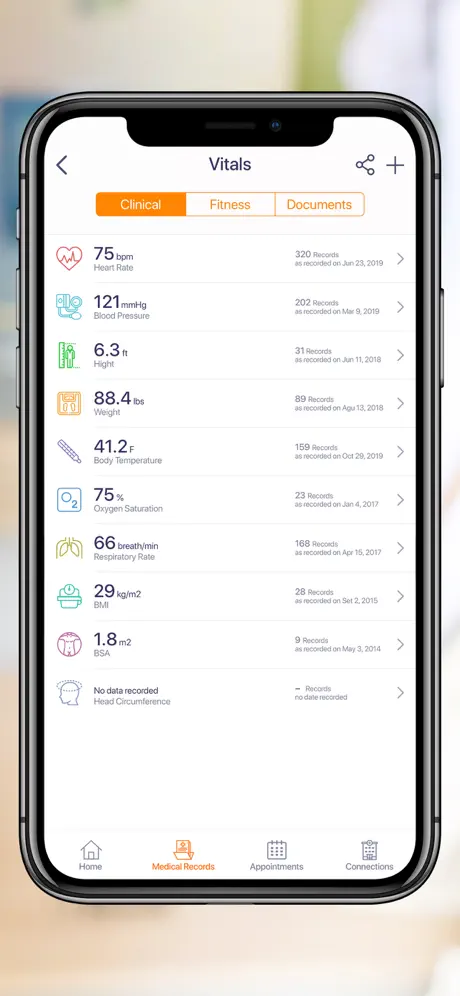

La aplicación permite a los pacientes acceder de forma segura a sus datos médicos o proxies familiares, programar citas, ver imágenes médicas, informes clínicos y de laboratorio de diferentes proveedores con la capacidad de descargar, archivar y compartir utilizando la tecnología de computación móvil más avanzada.

- Conecte con sus dispositivos usables o ingrese sus datos médicos manualmente

- Integración con HealthKit para recuperar los signos vitales del usuario para compartir con los médicos de la instalación